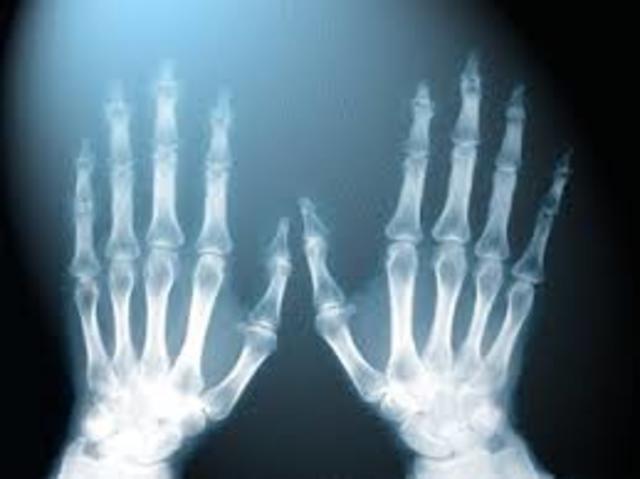

• Rayos X

Rayos X

Wilhelm Roentgen descubre accidentalmente los rayos X y lleva a cabo experimentos con la radiación de rayos catódicos (electrones). Se da cuenta de que los rayos pueden penetrar en papel negro opaco envuelto alrededor de un tubo de rayos catódicos, causando que una mesa cercana brille con fluorescencia. Su descubrimiento revoluciona la física y la medicina, lo que le valió el primer Premio Nobel de Física en 1901.

• Densitometría ósea

Densitometría ósea

La densitometría ósea es una prueba para determinar la densidad mineral ósea. Se puede realizar con rayos x, ultrasonidos o isótopos radiactivos. Sirve para el diagnóstico de osteoporosis. El test se realiza con el aparato que mide las imágenes y da una cifra de la cantidad mineral ósea por superficie.